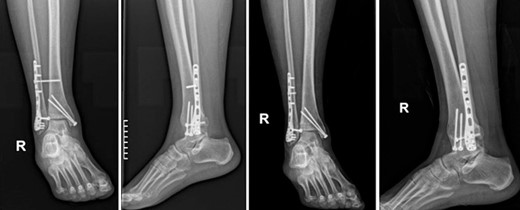

A 55-year-old female patient was admitted to the emergency department of our hospital due to an inability of weight bearing following a fall from standing height. Her medical history was unremarkable, with no significant records or regular medication use. Radiological evaluation revealed a trimalleolar fracture of the right ankle. Consequently, a cast was applied for pain management, and no weight-bearing was allowed on the affected limb (Fig. 1).

Anteroposterior and lateral X-ray of the ankle joint showing the trimalleolar fracture.